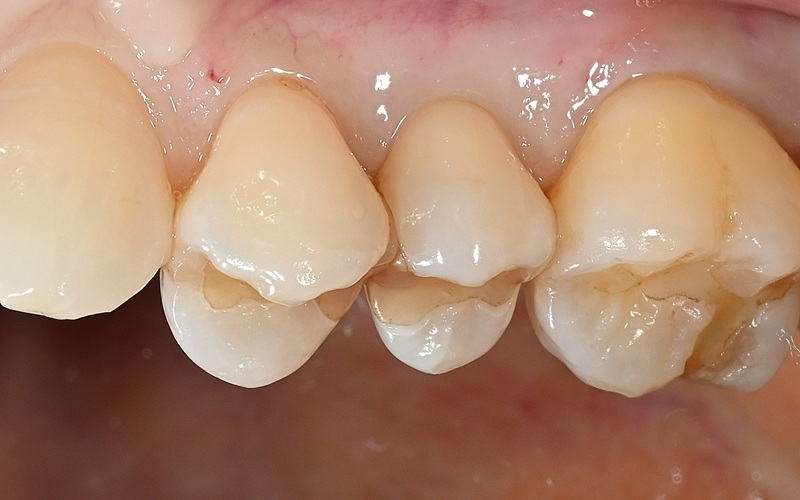

Case3

術前

ラバーダム防湿

正常歯髄をMTAセメントで保存

術後

| 治療名 | ダイレクトボンディング、MTAセメントを用いた歯髄保存 |

|---|---|

| 治療説明 | 歯髄に到達する大変大きな虫歯がありました。まだ若い患者であり、通常通り根管治療を行うと、歯質が薄くなり歯の寿命に大きく影響すると考えました。う蝕と感染の疑いがある歯髄を除去し,正常歯髄をMTAセメントを用いて保存した上で、ダイレクトボンディングにて歯の形を回復しました。 |

| 治療回数・期間 | 1回 |

| 副作用とリスク | 歯髄が感染し根管治療が必要となる可能性があります。レジンの着色、破折が起こり、研磨や再修復が必要となる可能性があります。 |

| 料金(税込) | MTAセメント:55,000円 ダイレクトボンディング:55,000円 |